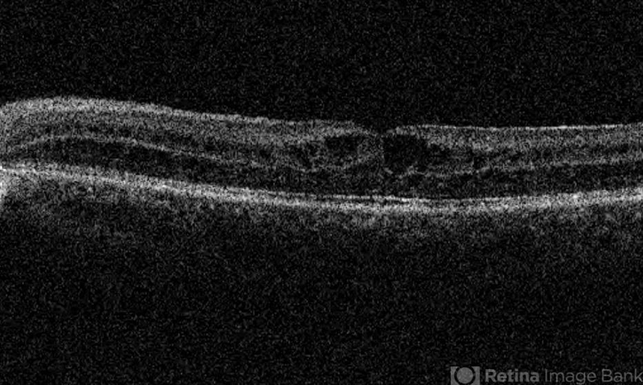

- x-linked retinoschisis (XLRS), foveal schisis, optical coherence tomography (OCT)

- OCT of the left eye of a 35-year-old man with x-linked retinoschisis. Please notice the foveal schisis.